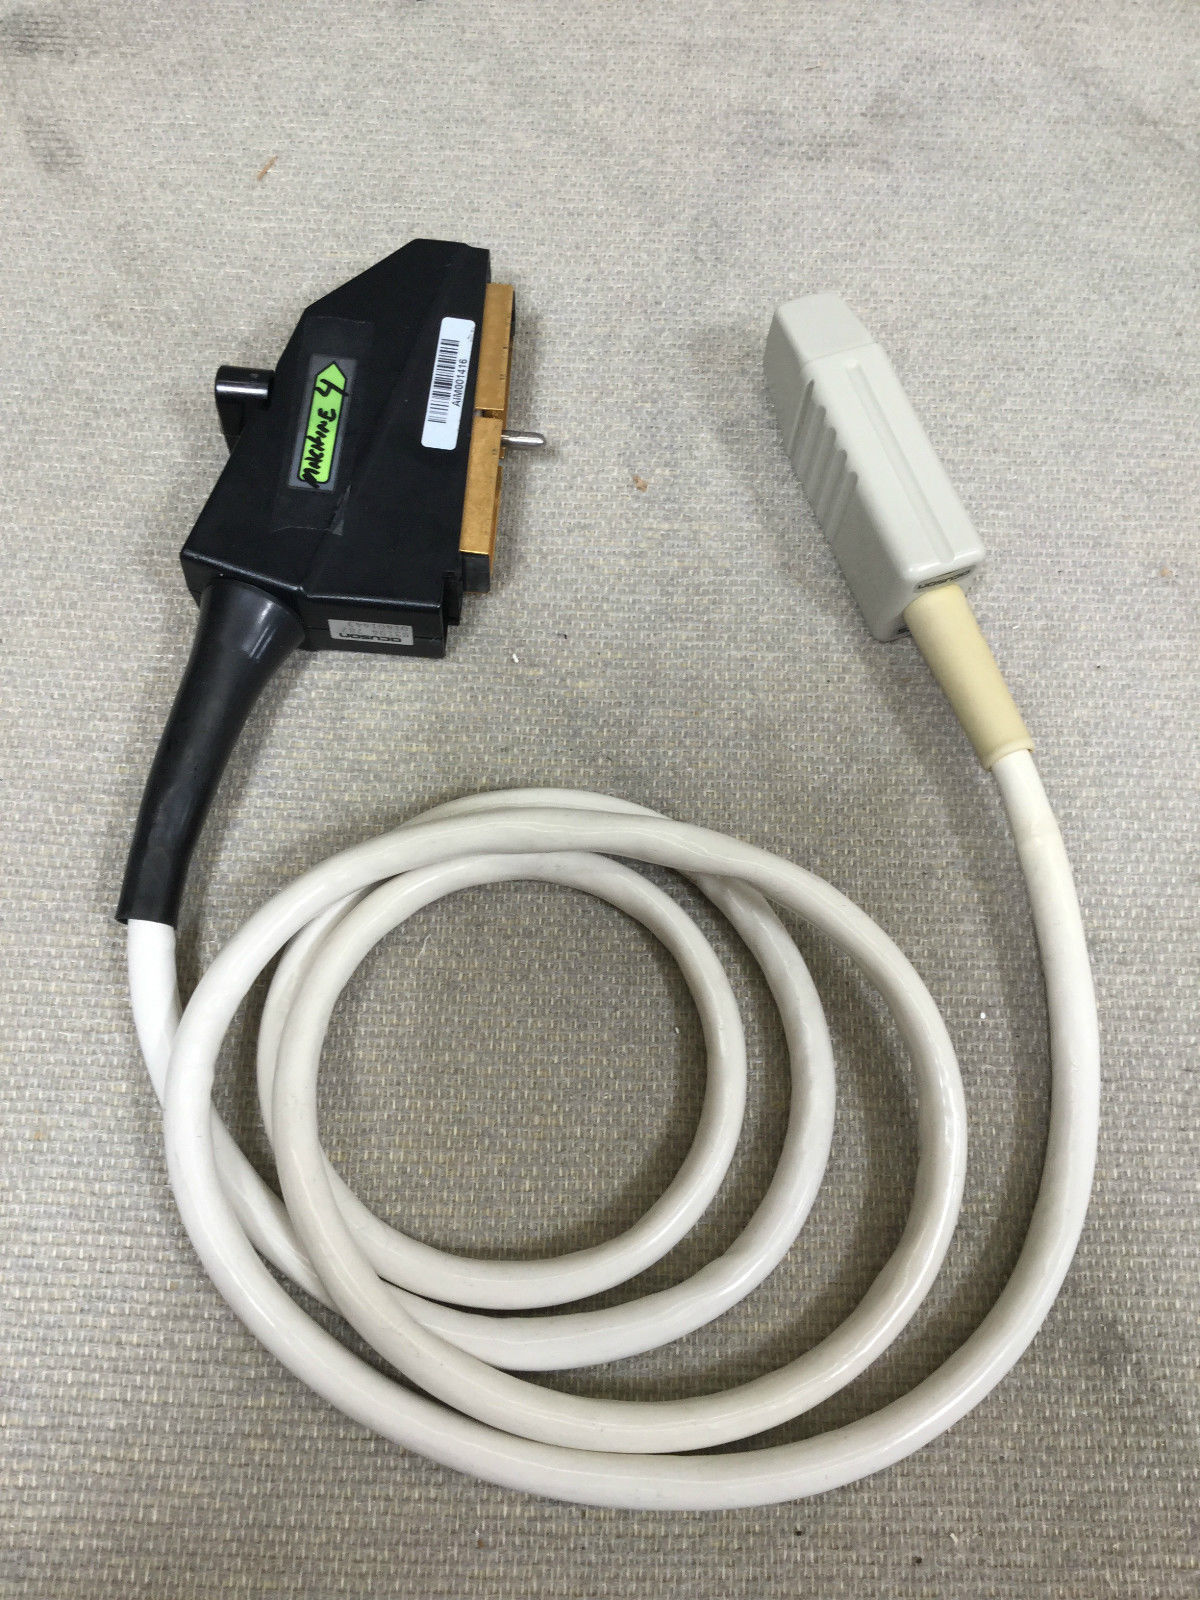

Acuson Linear Ultrasound Probe 7L3 08267217